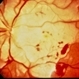

- Purtscher's retinopathy

- Fundus images of a 21-year-old woman with Purtscher's retinopathy. Mild visual improvement 20/200 OU vs. 20/400 OU .